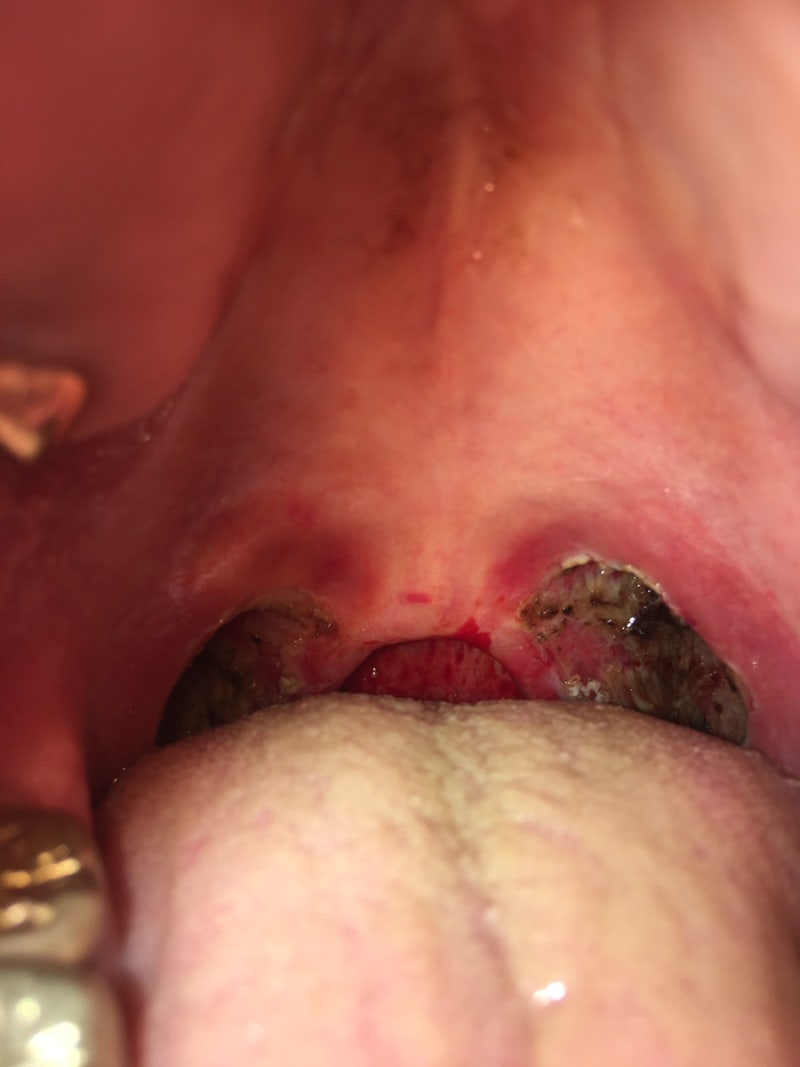

*11/21(월) 편도절제술 8일차 요약: 어제보다 더 아파!꾸준히 한 것: 냉찜질, 껌 씹는 새벽 4시에 깼는데 목이 너무 아프고 공복에 약을 한 대 더 먹었다. 그리고 아침에 일어나서 한 접시 더 먹는다. 일어났더니 어제보다 더 아팠어. 통증이 뒤로 왔다.목이 뜨거웠다.

오전까지만 해도 죽을 것 같았는데 오후 늦게 되면 약이 돌아가는지 살 것 같았다. 미역국이 너무 먹고 싶었는데 엄마가 어떻게 아셨는지 미역국을 끓여주셨어.통했다고 좋아하니까 먹고싶은거 있으면 말하라고~~~ 밥하고 죽처럼 먹었던 히히히~ 그리고 어제 엄마가 수육을 해주셨는데 어제는 아파서 못 먹었고 오늘 남은 걸 찢어 먹었다. 먹다 보면 목이 울퉁불퉁해지는 느낌이 들었던 우프 ^….연두부 반모도 든든히 먹어서 톳두부무침까지 먹었다. 아, 통닭 먹고 싶다.;;; 약이 돌면 생길것 같은 자신감이 생기는지 모르겠지만 혀가 쓰리고 부은 느낌이다